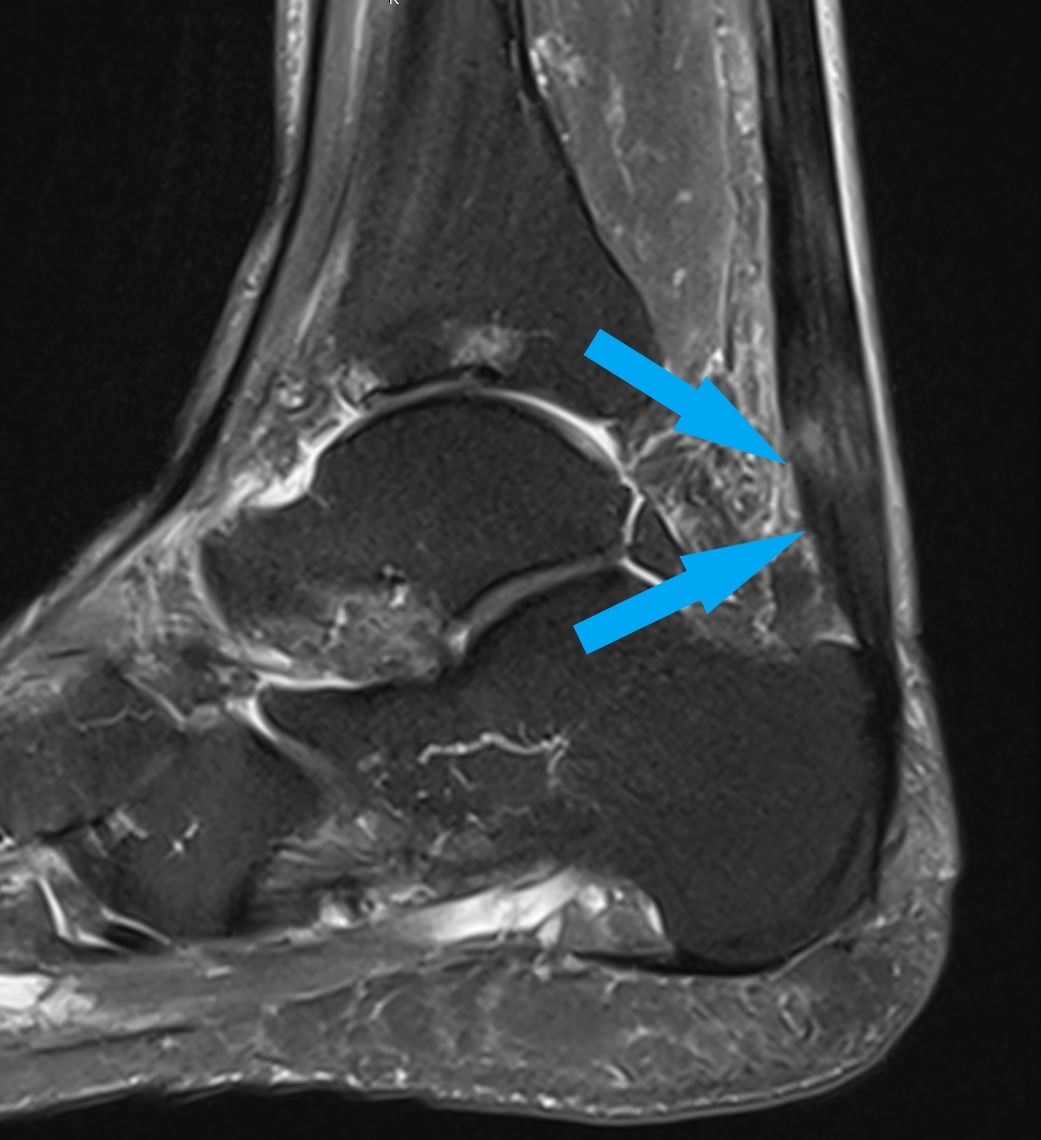

ausgeprägte Achillodynie mit Strukturdefekt in der Achillessehne